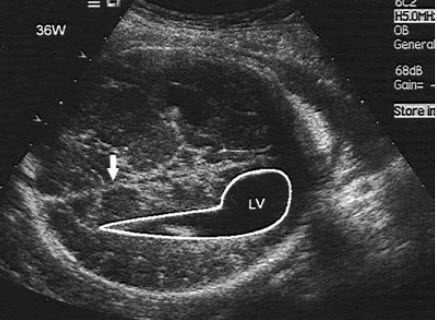

如图,36周胎儿,最可能的诊断是()

A.正常声像图

B.脑疝

C.脑积水

D.泪滴状侧脑室

E.以上都不是